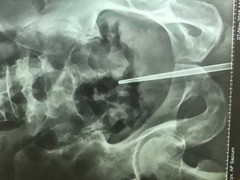

Một người đàn ông vừa phải vào bệnh viện nhờ bác sĩ cứu sau khi chơi dại nhét một cây đũa vào trong dương vật.